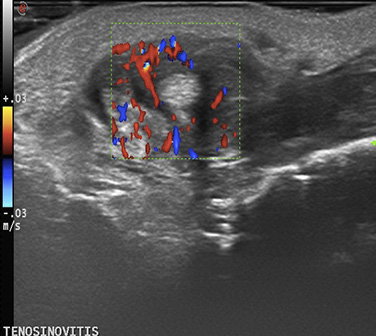

Ecografía en el paciente con psoriasis

La psoriasis en la actualidad es considerada una enfermedad inflamatoria multisistémica que necesita una evaluación integral de cada uno de los órganos diana que pueden ser afectados.

Desde la piel pasando por el sistema articular, la uña o incluso el sistema cardiovascular, la evaluación precoz de estos pacientes puede evitar un aumento en la morbimortalidad del paciente psoriásico.

La ecografía por su inocuidad, accesibilidad y disponibilidad es una herramienta en la valoración integral del paciente con psoriasis y nos ofrece la posibilidad de detectar las alteraciones en los órganos diana incluso en fases subclínicas con el debido entrenamiento.